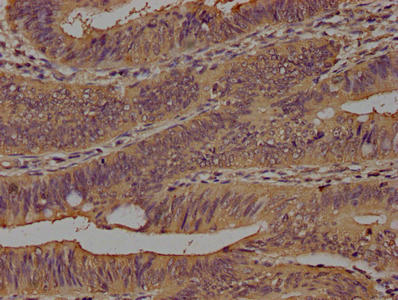

100 μg, 10 μg - Anti-Glucose Transporter GLUT1/SLC2A1 Antibody [orb259612]

FC, ICC, IF, IHC, IHC-Fr, WB

Human, Mouse, Rat

Rabbit

Polyclonal

Unconjugated